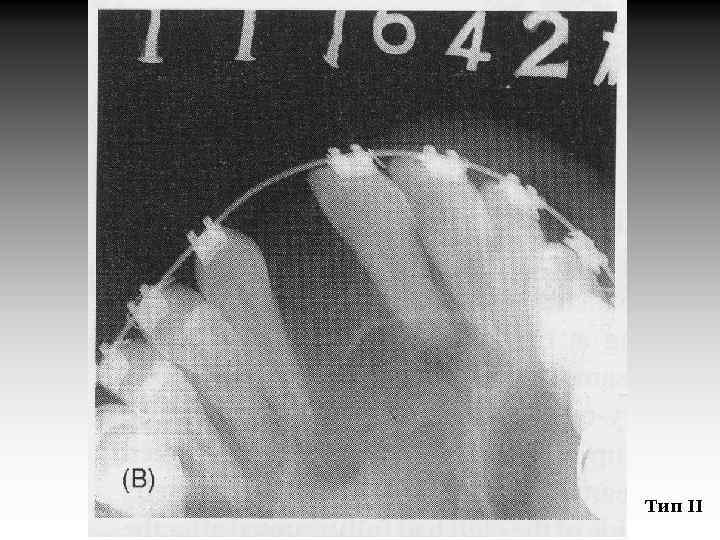

Результат ВКП находится в прямой зависимости от вида дефекта. Для наглядного сравнения после ВКП все расщелины были разделены на три группы: I. Расщелина губы и альвеолярного отростка (РГАО) II. Односторонняя расщелина губы и неба (ОРГН) III. Двусторонняя расщелина губы и неба (ДРГН) (Y. L. Jia, M. K. Fu, L. Ma. Peking University, 2006)

Тип II

Таблица 1. Результат ВКП в зависимости от прорезывания клыков и типа костного дефекта, % Вид расщелины РГАО ОРГН ДРГН 96 83 68 94 95 91 4 17 32 6 5 9 Тип Бергланда Благоприятный исход (Тип I и II) Прорезавшийся клык Непрорезавшийся клык Неблагоприятный исход (Тип III и IV) Прорезавшийся клык Непрорезавшийся клык (Y. L. Jia, M. K. Fu, L. Ma. Peking University, 2006)